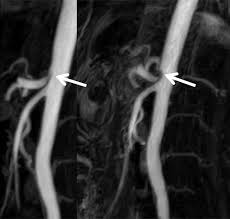

A B A 54 Year Old Female Patient With Celiac Artery Compression Download Scientific Diagram